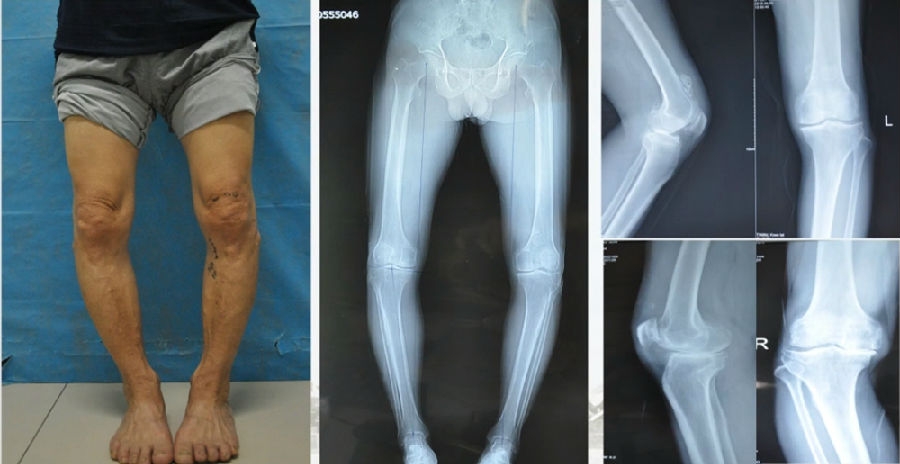

典型病例,女性,56岁,农民右膝内翻18度。

术前影像

典型病例,男性,65岁,农民,双膝内翻16度。

典型病例,男性,57岁,农民,左膝疼痛3年。

术前

术前影像资料

典型病例2,男性,52岁,双膝疼痛,低磷佝偻病,复合畸形。